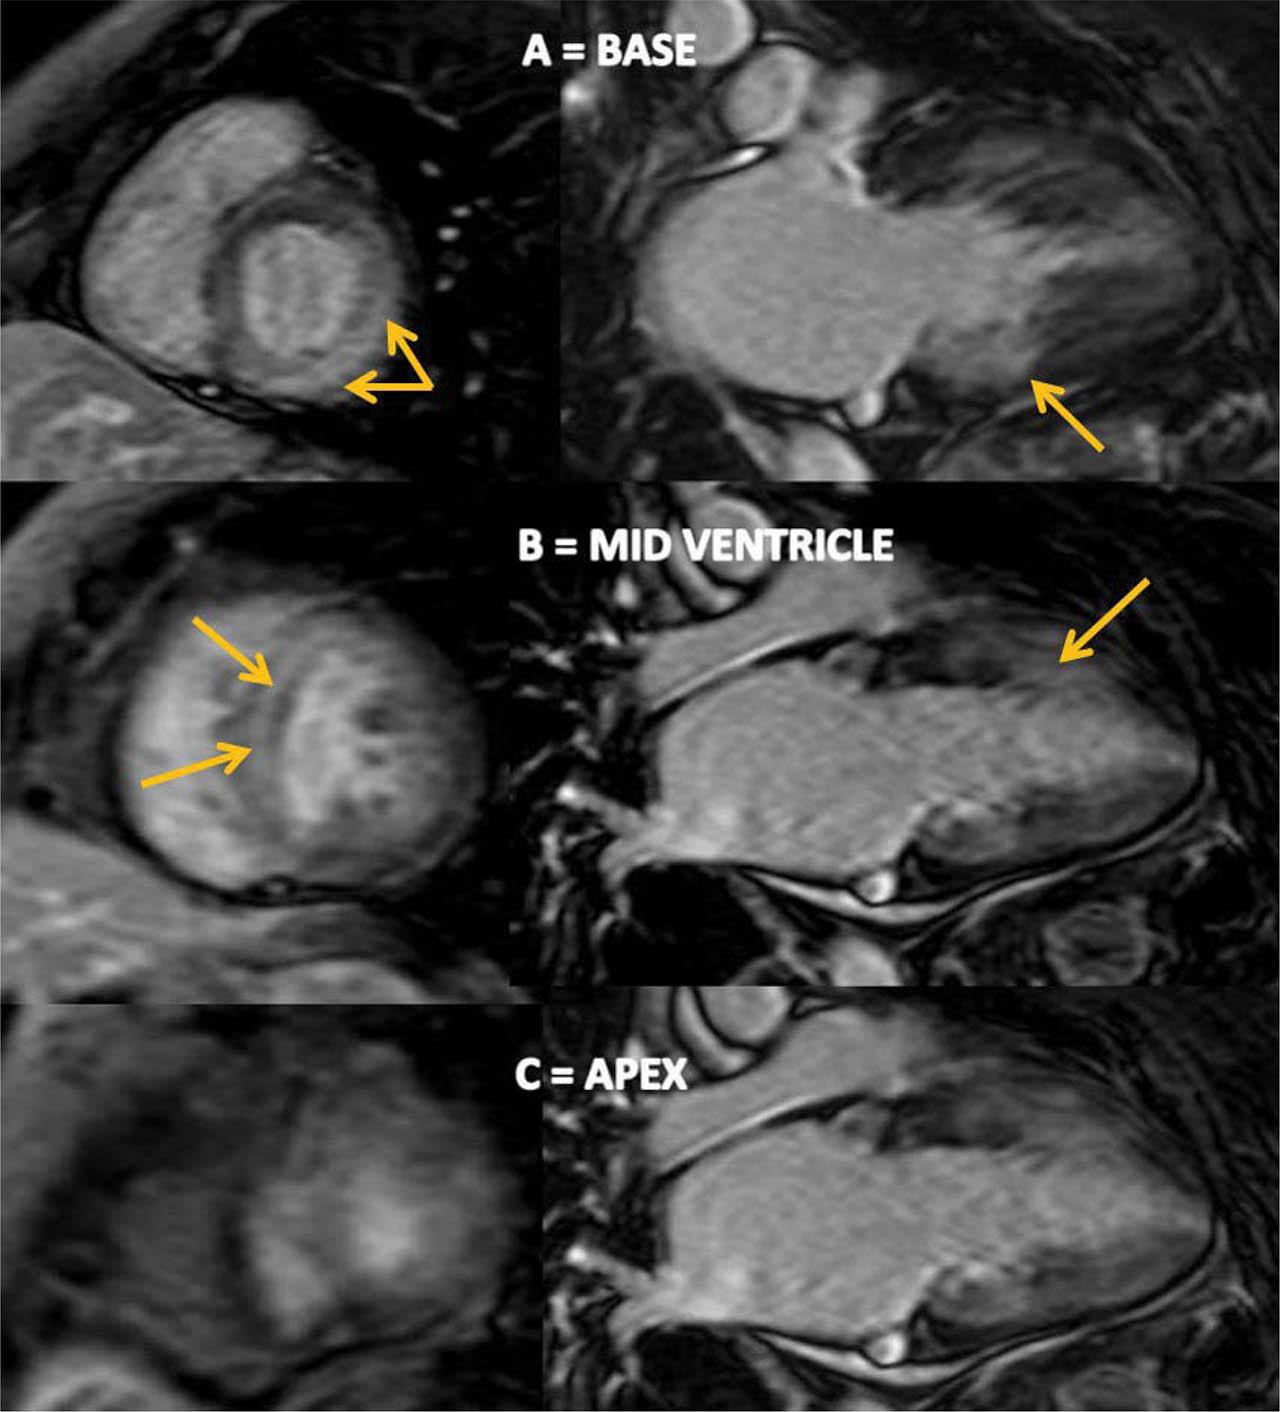

Up to this point, the diagnosis was HF with midrange EF, functional NYHA class IV, due to restrictive cardiomyopathy. Serum cardiac biomarkers were persistently elevated. Moreover, the pseudo-infarct pattern in the anterior and inferior leads on ECG, the discrepancy between low-voltage QRS and increased LV wall thickness on TTE, together with DD grade 3, and apical sparing pattern on STE were suggestive for CA. The patient underwent cardiac magnetic resonance (CMR) which confirmed LV hypertrophy and LVEF of 45%, non-dilated ventricles, enlarged atria (LAVi=66 ml/m2), and 5 mm pericardial effusion adjacent to LV lateral wall. CMR showed diffuse subendocardial late gadolinium enhancement (LGE) at the base and mid-ventricle in the LV and along mitral and tricuspid valve, without LGE involvement of the LV apex and LA (Figure 5). An increase in RV wall thickness was also noted but without LGE (Figure 6). The Query Amyloid Late Enhancement (QALE)12 score was 4 point, highly suggestive of cardiac AL amyloidosis. For histological confirmation, we decided to have a double biopsy, in order to increase sensitivity. Abdominal and rectal pad biopsy were taken and showed homogenous extracellular fibrils positive for Congo red staining and positive for green birefringence, specific for amyloid deposits (Figure 7). Once the diagnosis of CA was made, the next step was to identify the type of amyloid, in order to plan the appropriate treatment. Although serum and urine electrophoresis with immunofixation were negative, a serum free light chains assay showed a marked increase of λ light chains, indicating the presence of a population of plasma cells producing clonal λ free light chains. Because AL amyloidosis was suspected based on CMR findings, a bone marrow biopsy was performed and showed a medullary plasmacytosis (30%), a typical finding for AL amyloidosis.

Figure 5

Cardiac magnetic resonance images showing A and B diffuse subendocardial LGE at the base and mid-ventricle in the left ventricle (yellow arrows). C no LGE of the apex. LGE: late-gadolinium enhancement.

CMR is also useful for diagnosing CA, particularly when performed with the use of the gadolinium as an imaging agent9. In amyloidosis, LGE can occur in 3 possible patterns: no LGE, sub-endocardial enhancement, and transmural enhancement14. The pattern of LGE may help in differentiating the two subtypes of CA, with transmural LGE being more prevalent in TTR amyloidosis as opposed to sub-endocardial LGE, which appears to be more prevalent in AL amyloidosis14. Moreover, the Query Amyloid Late Enhancement (QALE) score was recently validated as a prognostic score in patients with AL amyloidosis14. QALE score was based on patterns of LGE in the LV at 3 levels (base, mid ventricle, and apex) and in the RV free wall. The maximum LV LGE score at each level is 4 (maximum LV LGE score 12), plus 6 if RV LGE is present and ranged from 0 (no LGE in the left or right ventricle) to 18 (global transmural LV LGE with RV involvement)14. A cut-off of 9 was proved to differentiate prognosis in AL amyloidosis patients with a subendocardial LGE pattern15. Patients with a subendocardial LGE-QALE score < 9 have a better prognosis, similar to the patients with no apparent cardiac involvement and no LGE, whereas a value ≥ 9 implies a worse prognosis, similar to the transmural LGE15. CMR showed subendocardial LGE in our patient, highly suggestive for AL amyloidosis, and the QALE score was 4, with subendocardial LGE observed at the base and mid-cavity of LV, without RV LGE.